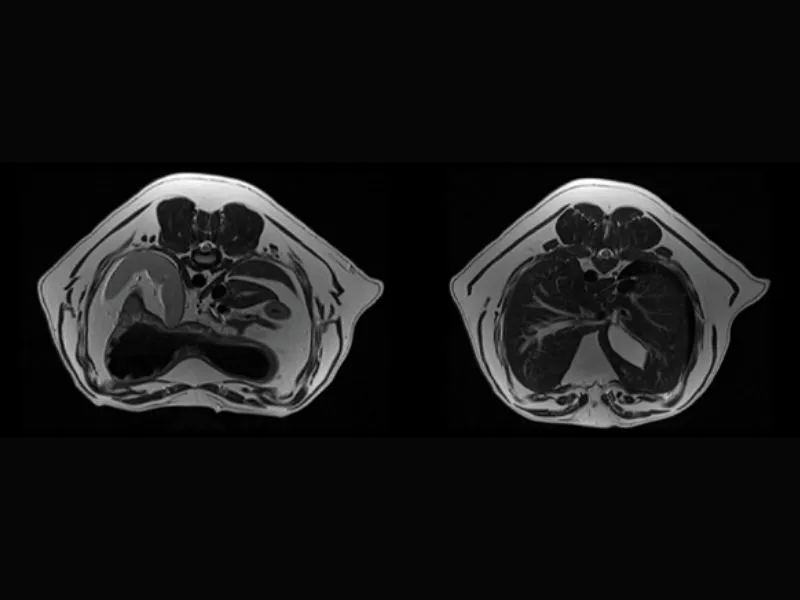

Vet-MR Grande ELITE – Brain2 Transeverse FSE T2